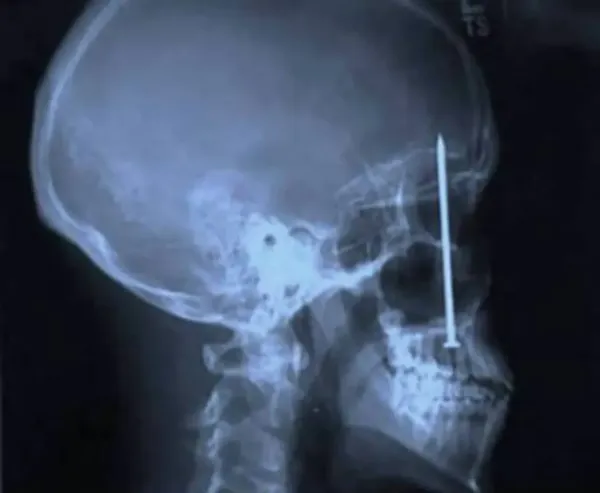

(4)4인치 못:패트릭 롤러라는 남성은 치통을 호소하며 병원에 갔지만 원인을 알지 못했다. 엑스레이 촬영결과 이 남자는 자기도 모르는 사이에 4인치 못을 자신의 입천장에 박아넣은것이다.

(7)칼:이 병사의 눈썹 위에는 4인치 길이의 칼이 꽂혀진 상태다. 다행히 아무런 문제 없이 수술을 마쳤다고 한다.